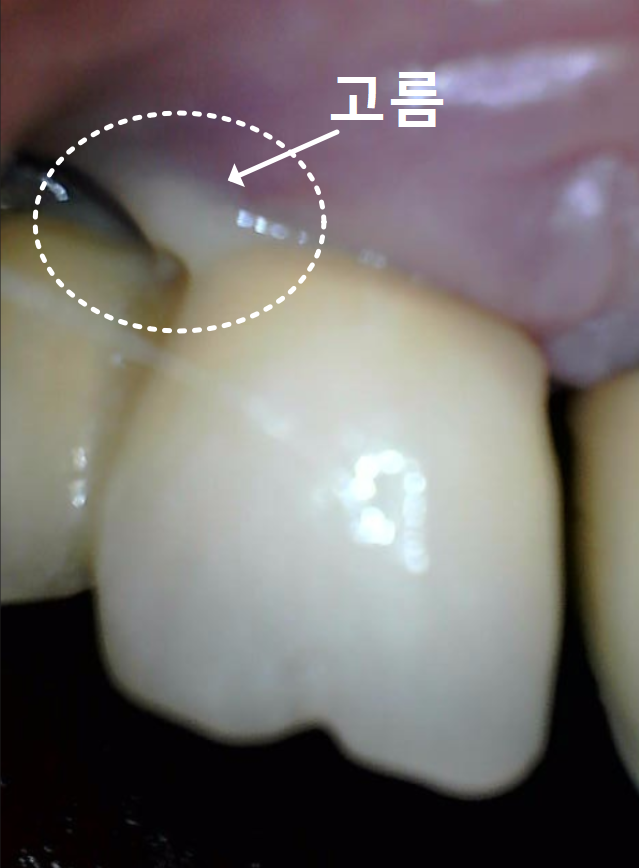

입안을 자세히 살펴보니,

보철물이 많이 닳아 낮아지면서

임플란트 나사 구멍이 드러나 있었고,

주변 잇몸은 붉게 부어올라

살짝만 건드려도 고름이 배어 나오는 상태였습니다.